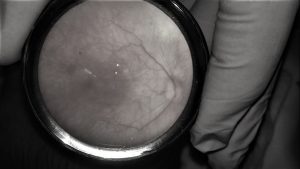

Vascularización incompleta